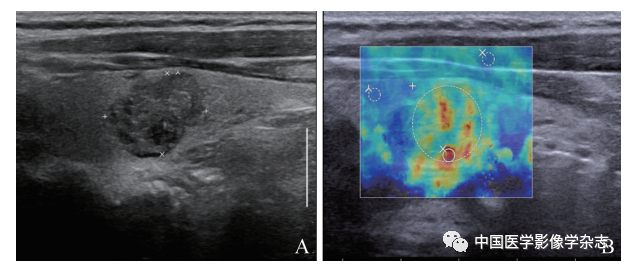

49个恶性结节中,TIRADS和SWE均诊断为恶性27例;TIRADS诊断为恶性、SWE诊断为良性10例;TIRADS诊断为良性、SWE诊断为恶性9例(图2)。

图2 BSRTC Ⅲ类、术后病理证实为恶性结节声像图。A. TIRADS分类诊断为阴性(TIRADS 4A类);B. SWE诊断为阳性(Emax=97.8 kPa)